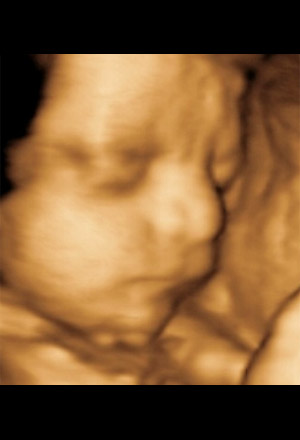

| | 8 / 12 Month 7 (Week 28)

This month marks the beginning of the third trimester and the fetus weighs about 1 kilogram (2.2 pounds) and is about 38 cm (14.8 inches) long. At about week 28 most babies begin to start turning head down. As the room becomes more crowded, you may feel smaller movements from the baby, compared to the wild kicks from before. The baby can sense light and dark in the uterus, and this may also affect its sleep and wake cycles. If the baby were born prematurely now, there's a good chance of survival with the help of medical technology. Ask your doctor about preterm labor warning signs. Now is a good time to register for birthing classes to prepare you for labor and delivery, and newborn care.